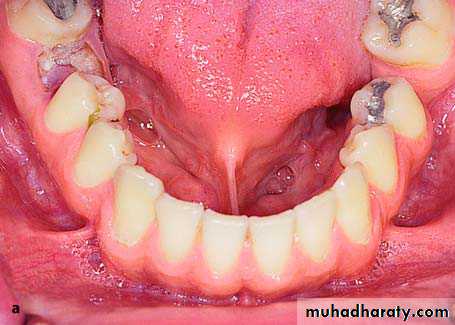

a Radiograph of maxillary teeth, after whose removal smoothing of alveolar bone is required. b Clinical photograph of teeth to be extracted

preprosthatic surgery

Diagrammatic illustration (a) and clinical photograph (b) of gross intraseptal irregularities after multiple tooth extractions